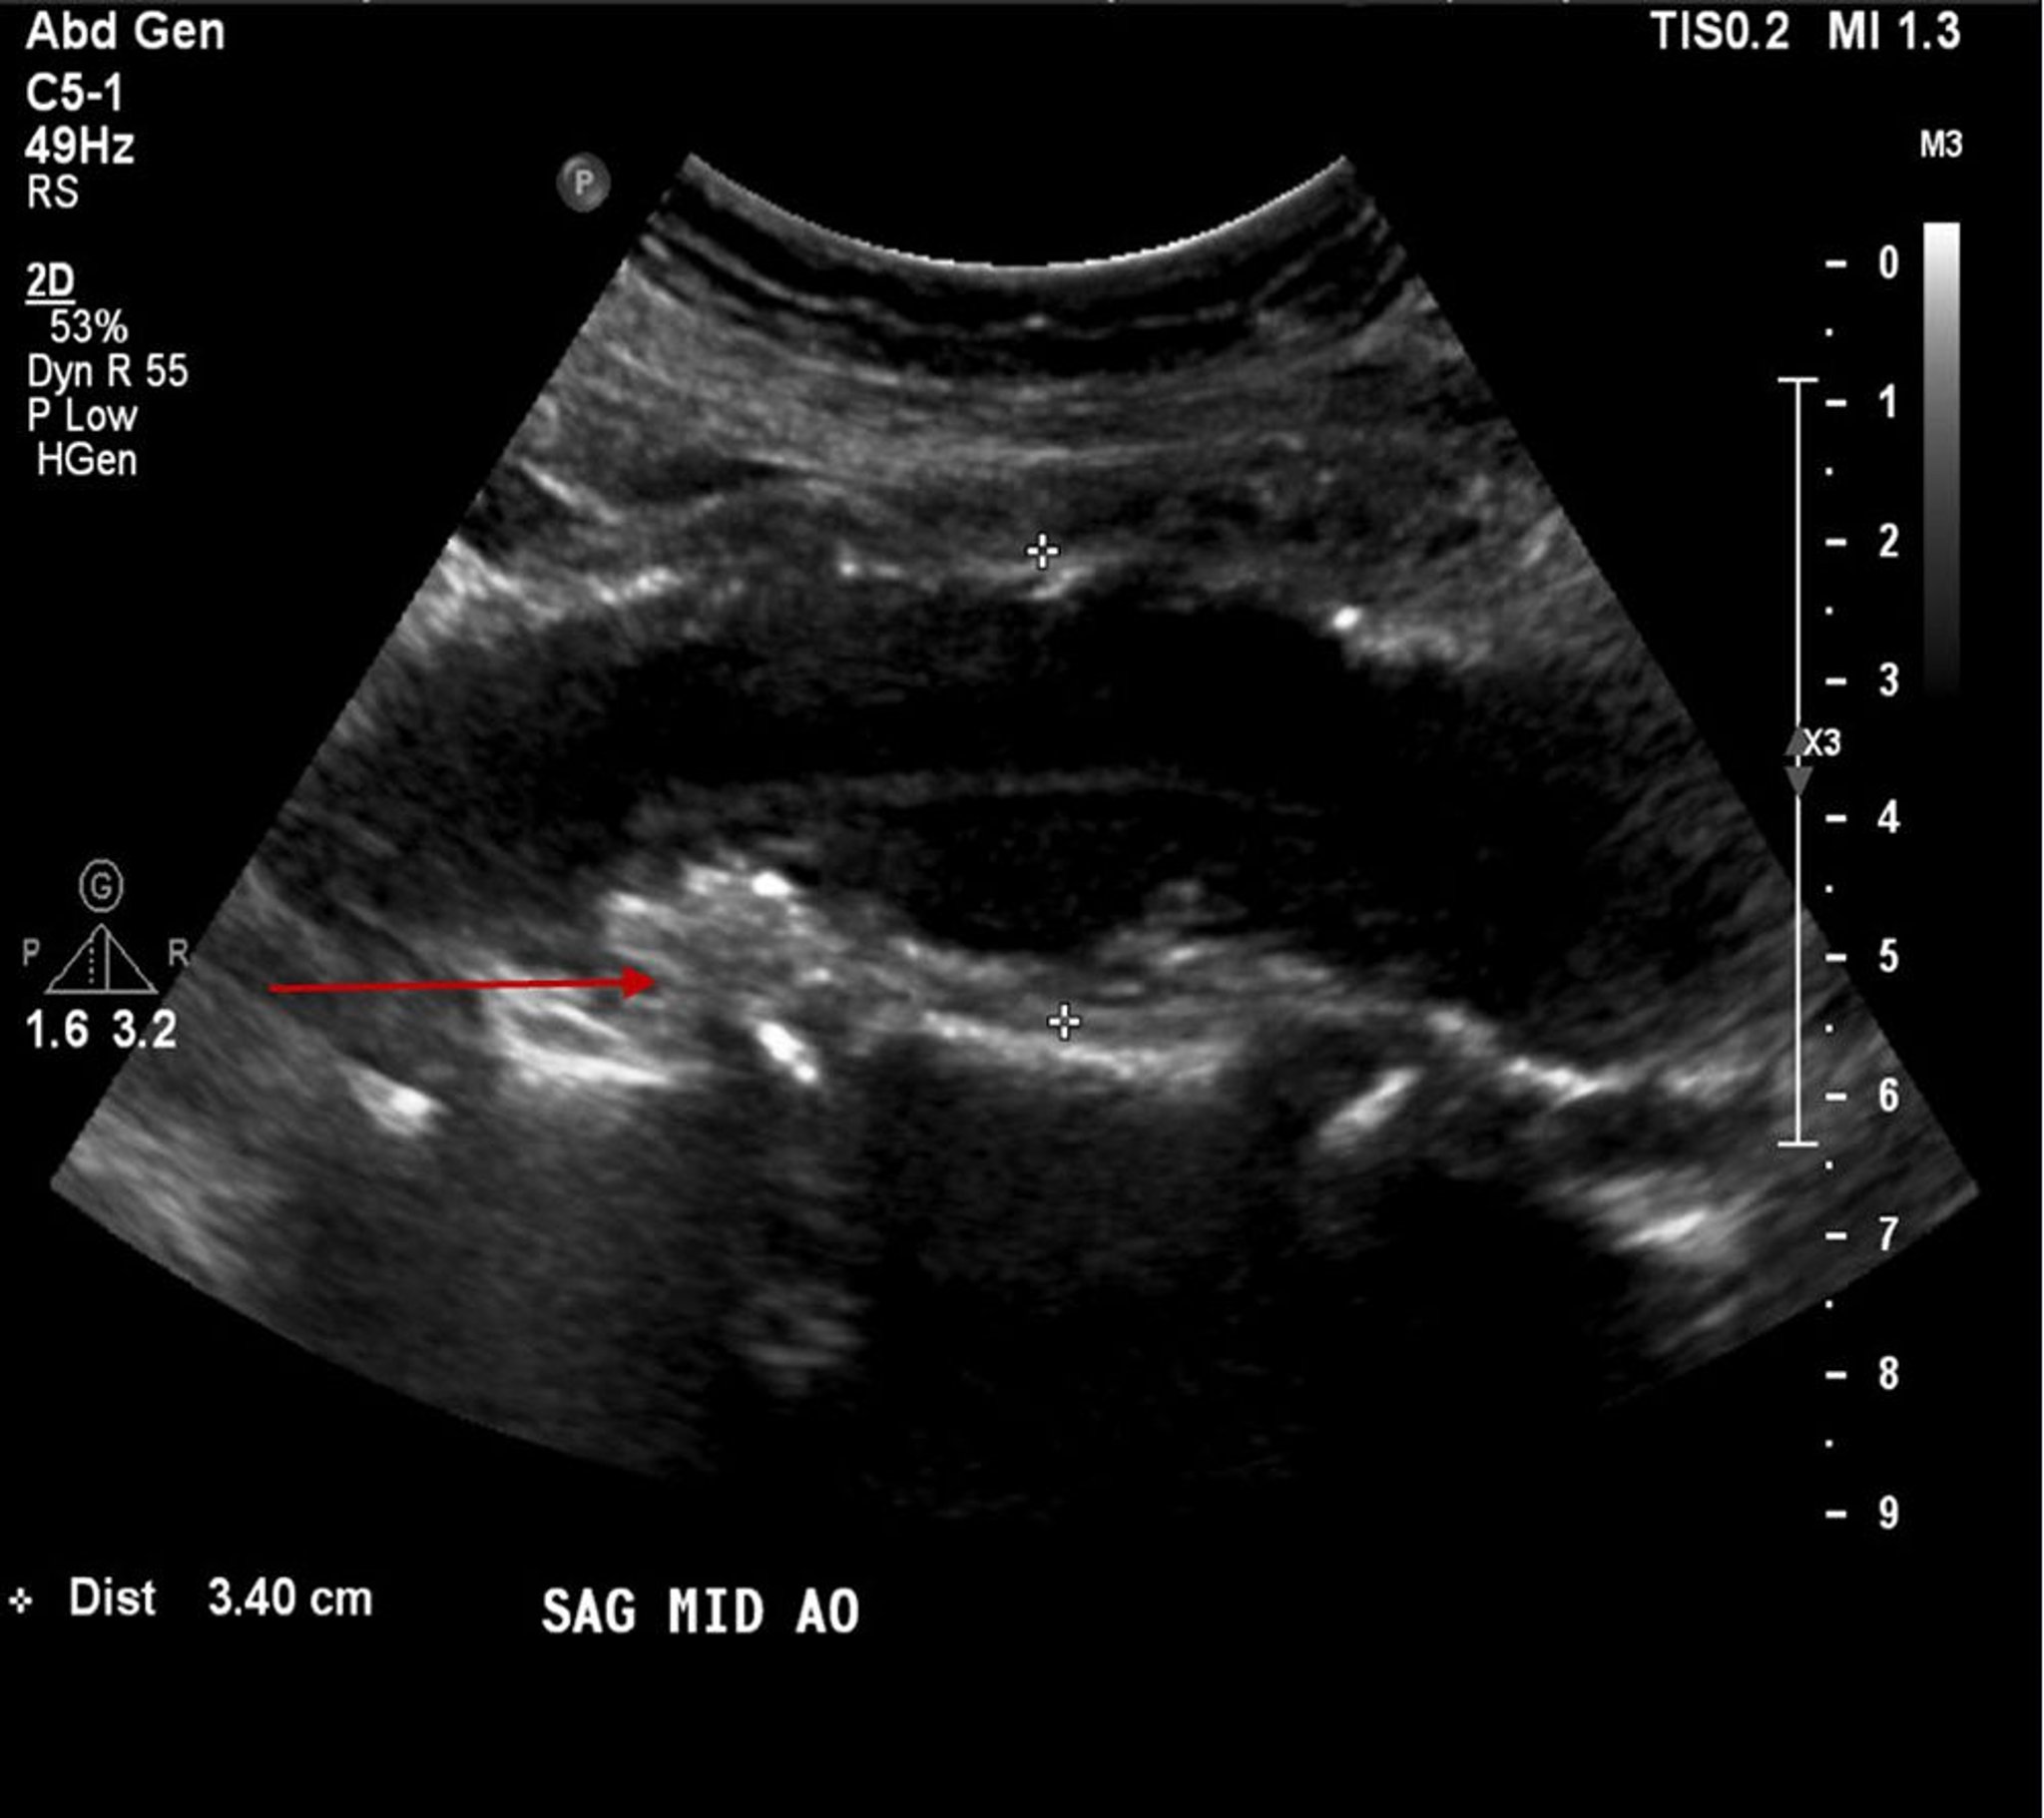

Аневризма брюшного отдела аорты (УЗИ)

Этот пациент имеет аневризму брюшной аорты размером 3,4 см (между белыми крестами), наблюдаются также атеросклеротическая бляшка или пристеночный тромб (красная стрелка).